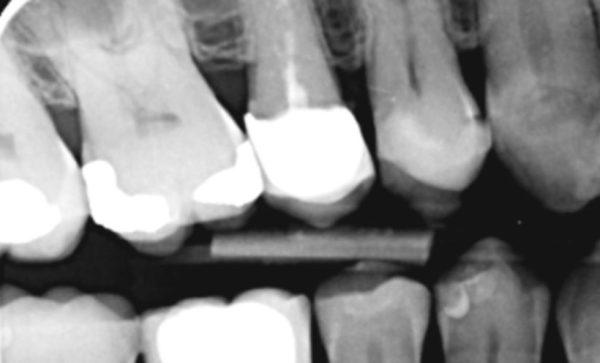

I have been a patient of Dr Verma for 8 years, my treatment has included crowns and an implant. Treatment plans and options are explained to me clearly, my concerns and anxieties are allieviated without hurry or pressure in a gentle and reassuring way. I feel my patient satisfaction is valued.

Sukal has been my dentist for many years, from simple check ups to a dental implant! I have always felt comfortable in the dentist chair and happily watched the TV on the ceiling while work is done on my teeth and never once felt any pain and always felt comfortable. I would never go anywhere else! Thank you all for being kind, caring and helpful at all times :-) Sarah Galloway